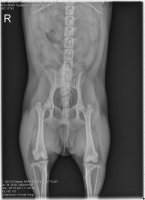

아이를 키우다 보면 어느날 O다리나 X다리, 안짱다리 등으로 걸음걸이가 이상하다는 것을 주위사...틀어주는 운동 치료를 하며 바른 자세교정과 발교정기를 이용한 교정 치료를 합니다. 안짱다리를 시기를

레그모아 : O다리, X다리 교정기 약간 O다리형인 나는 다리에 약간 컴플렉스가 있다. 그래서 다리 교정기를 이것 저것 많이 찾아보곤 했었는데, 너무 간편하고 짱짱하게 다리를 잡아주는 미용기기가

척추측만증을 위한 교정기라던가 O다리 교정기는 들어봤는데 제가 한번 어떤건지 알려드릴게요 ㅋㅋㅋㅋㅋㅋ 연골 느낌!?!? 그리고 구멍 보이시죠? 부끄럽고 더럽게 생각하지마세요ㅠ 저렇게